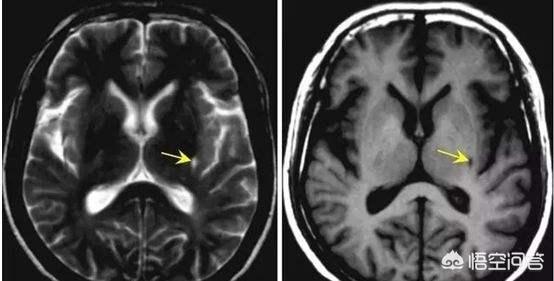

海綿状脳梗塞は、一般的な脳血管障害の一つであり、持続性高血圧と小動脈硬化に起因する特殊な脳血管障害で、直径100〜400μmの深部貫通枝の閉塞による微小梗塞である。末期には、軟化した微小病巣から壊死組織が除去され、小さな嚢胞状の空洞が残るため、海綿状脳梗塞と呼ばれる。

病理診断名にちなんで命名され、脳の新鮮または古い深在性小梗塞の総称である。好発部位は大脳基底核と大脳皮質基底部であり、発生頻度は側坐核、尾状核、視床、大脳皮質、内被殻、白質であり、大脳皮質と小脳皮質は発生しない。

脳梁性脳梗塞は、脳深部の細動脈の病変による血管の閉塞によって起こる。 細動脈が供給する脳の領域は比較的小さいので、脳梗塞の領域も小さい。通常、脳梗塞は2mm-5mm間、最大指の爪の半分の大きさ。。

海綿状脳梗塞の病変は、細くて深い動脈の閉塞であるため、メロンの種がメロンの真ん中に集中しているように、脳の中心部に点在している。

海綿状脳梗塞は、長期高血圧、高脂血症、糖尿病などの危険因子の役割で、脳組織の小さな貫通動脈を指し、血管壁の病変、最終的には内腔の閉塞、その結果、遠位脳組織の虚血と無酸素性壊死、貪食による壊死脳細胞、除去、小さな空洞の形成、したがって、我々は海綿状脳梗塞と呼ぶ、梗塞の大きさの梗塞巣は、一般的に1.5〜2センチメートル以下です。2cm以下である。